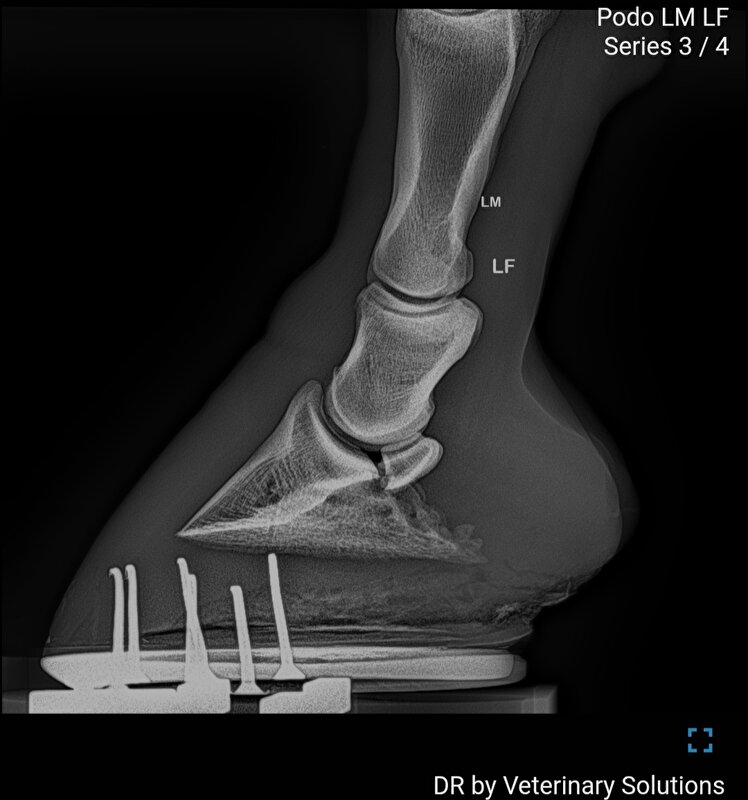

lianne125 schreef:Zijn er stand/ balansfoto's gemaakt van de voeten? Zo nee is dat nog wel een interessante optie die niet veel kost. Zeker omdat je het hebt over een naar achter gebroken voetas en ondergeschoven verzenen. Icm met de teen opwippen doet mij sterk denken aan NPA's. Ik ben benieuwd wat er op dit moment aan beslag onder zit.

Suzanne F. schreef:Het paard heeft duidelijk problemen met de hoefstanden wat inwendig dus problemen geeft. Je kan het nog een tijdje aankijken maar als de irritaties inwendig niet minder worden dan wordt het moeilijk. Ik lees over irritaties aan het hoefbeen en het kootgewricht. Ik ben wel benieuwd of dat inmiddels minder is. Als dat duidelijk minder is en het paard is nog even kreupel dan komt het toch ergens anders vandaan.